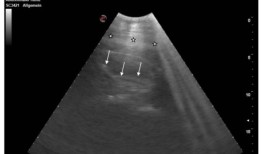

布莱克浦动物园正在准备迎接八只不那么小的脚的到来! 两头怀孕的大象接受了类似于人类的超声波...